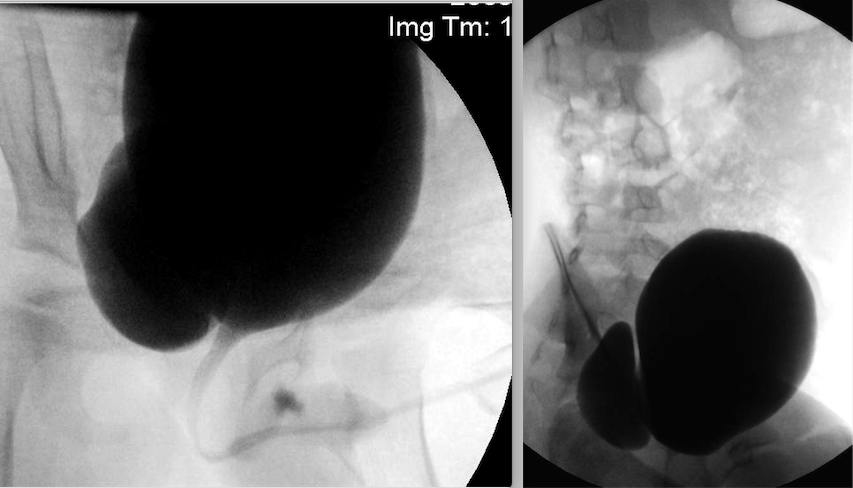

A two-year-old boy has foul smelling urine and dysuria. A urine culture grew pan-sensitive coagulase negative Staphylococcus. His symptoms resolved with antibiotics and a renal ultrasound is normal. A VCUG is shown. The next step is:

5

The imaging reveals a large congenital right sided bladder diverticulum. There is no evidence of bladder outlet obstruction or valves. This is a source of stasis (incomplete bladder emptying) that will not spontaneously resolve. Smaller periureteral diverticula are associated with dysfunctional elimination and are not treated surgically but in this case diverticulectomy is indicated. Based upon the size of the diverticulum, this child will almost certainly have recurrent infections. As such, prophylactic antibiotics or observation are not appropriate options in a pediatric patient. The diverticulum arises cephalad and lateral to the ureteral orifice. The ureter and diverticulum are intimately associated. The ipsilateral ureter should be reimplanted if it is near or included in the diverticulum whereas a diverticulum on the lateral bladder wall or dome (urachal diverticulum) can be resected without ureteral reimplantation. Both can be performed extravesically with entry into the bladder only when the diverticulum is entered.